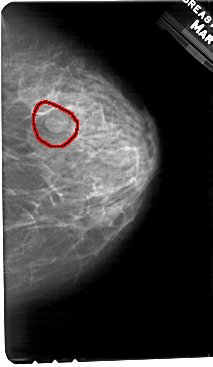

A_1363_1.RIGHT_CC

RIGHT_CC LINES 5491 PIXELS_PER_LINE 3181 BITS_PER_PIXEL 12 RESOLUTION 43.5 OVERLAY

FILE: A_1363_1.RIGHT_CC.OVERLAY

TOTAL_ABNORMALITIES 1

ABNORMALITY 1

LESION_TYPE MASS SHAPE OVAL MARGINS CIRCUMSCRIBED-OBSCURED

ASSESSMENT 4

SUBTLETY 4

PATHOLOGY BENIGN

TOTAL_OUTLINES 1

BOUNDARY